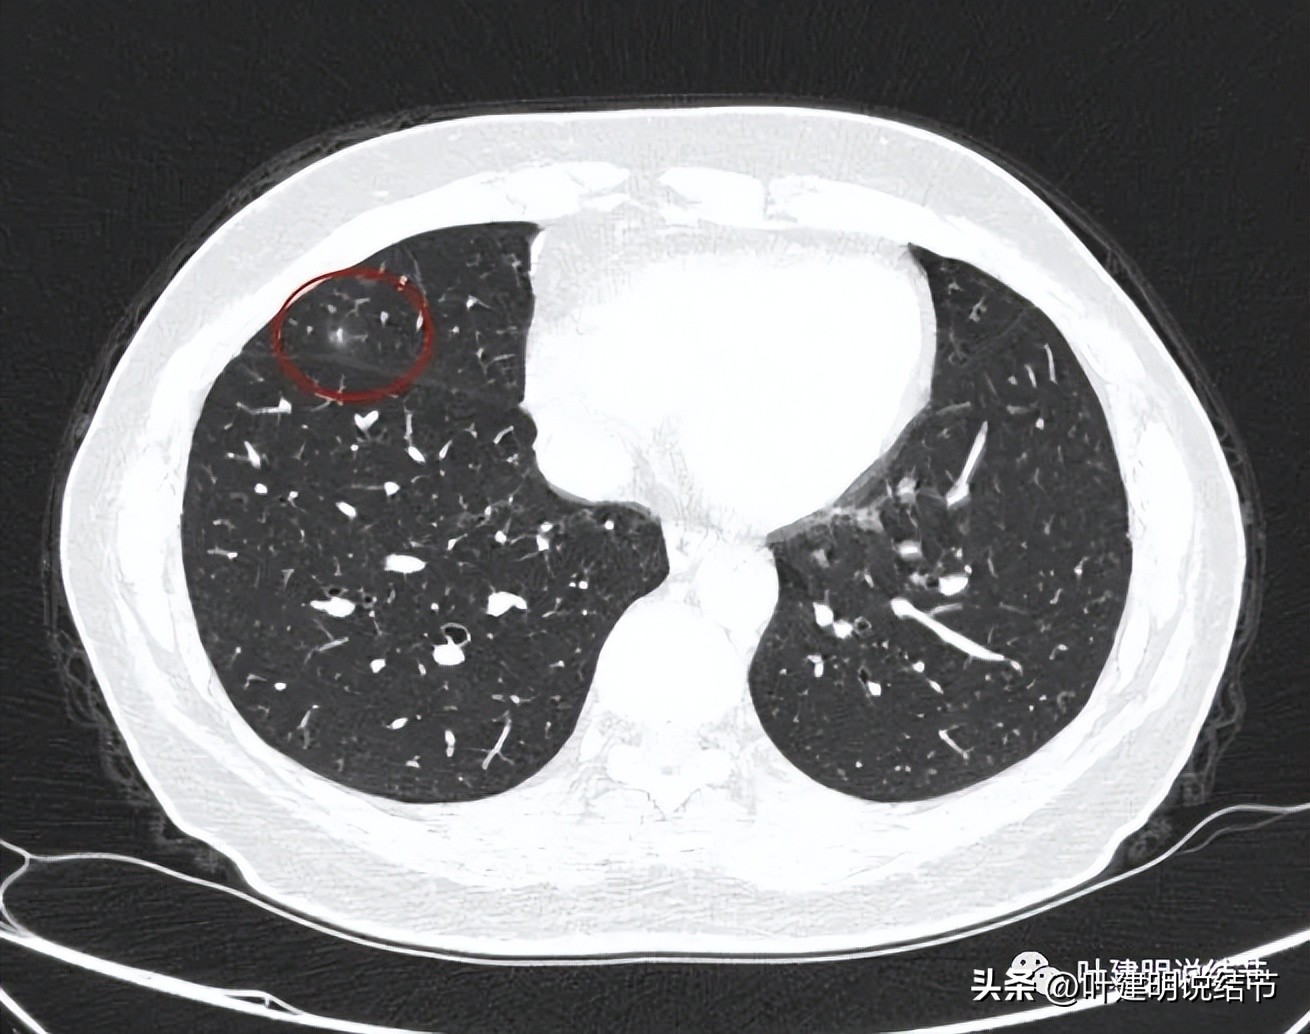

中叶病灶前后对比:

上图是2020年5月时的

上图是2021年12月时的

上图是2023年3月时的

可见持续存在并无好转,似乎略有进展,当然不是太明显。形态真的与左下的类似,只是左下的有空腔,它没有。